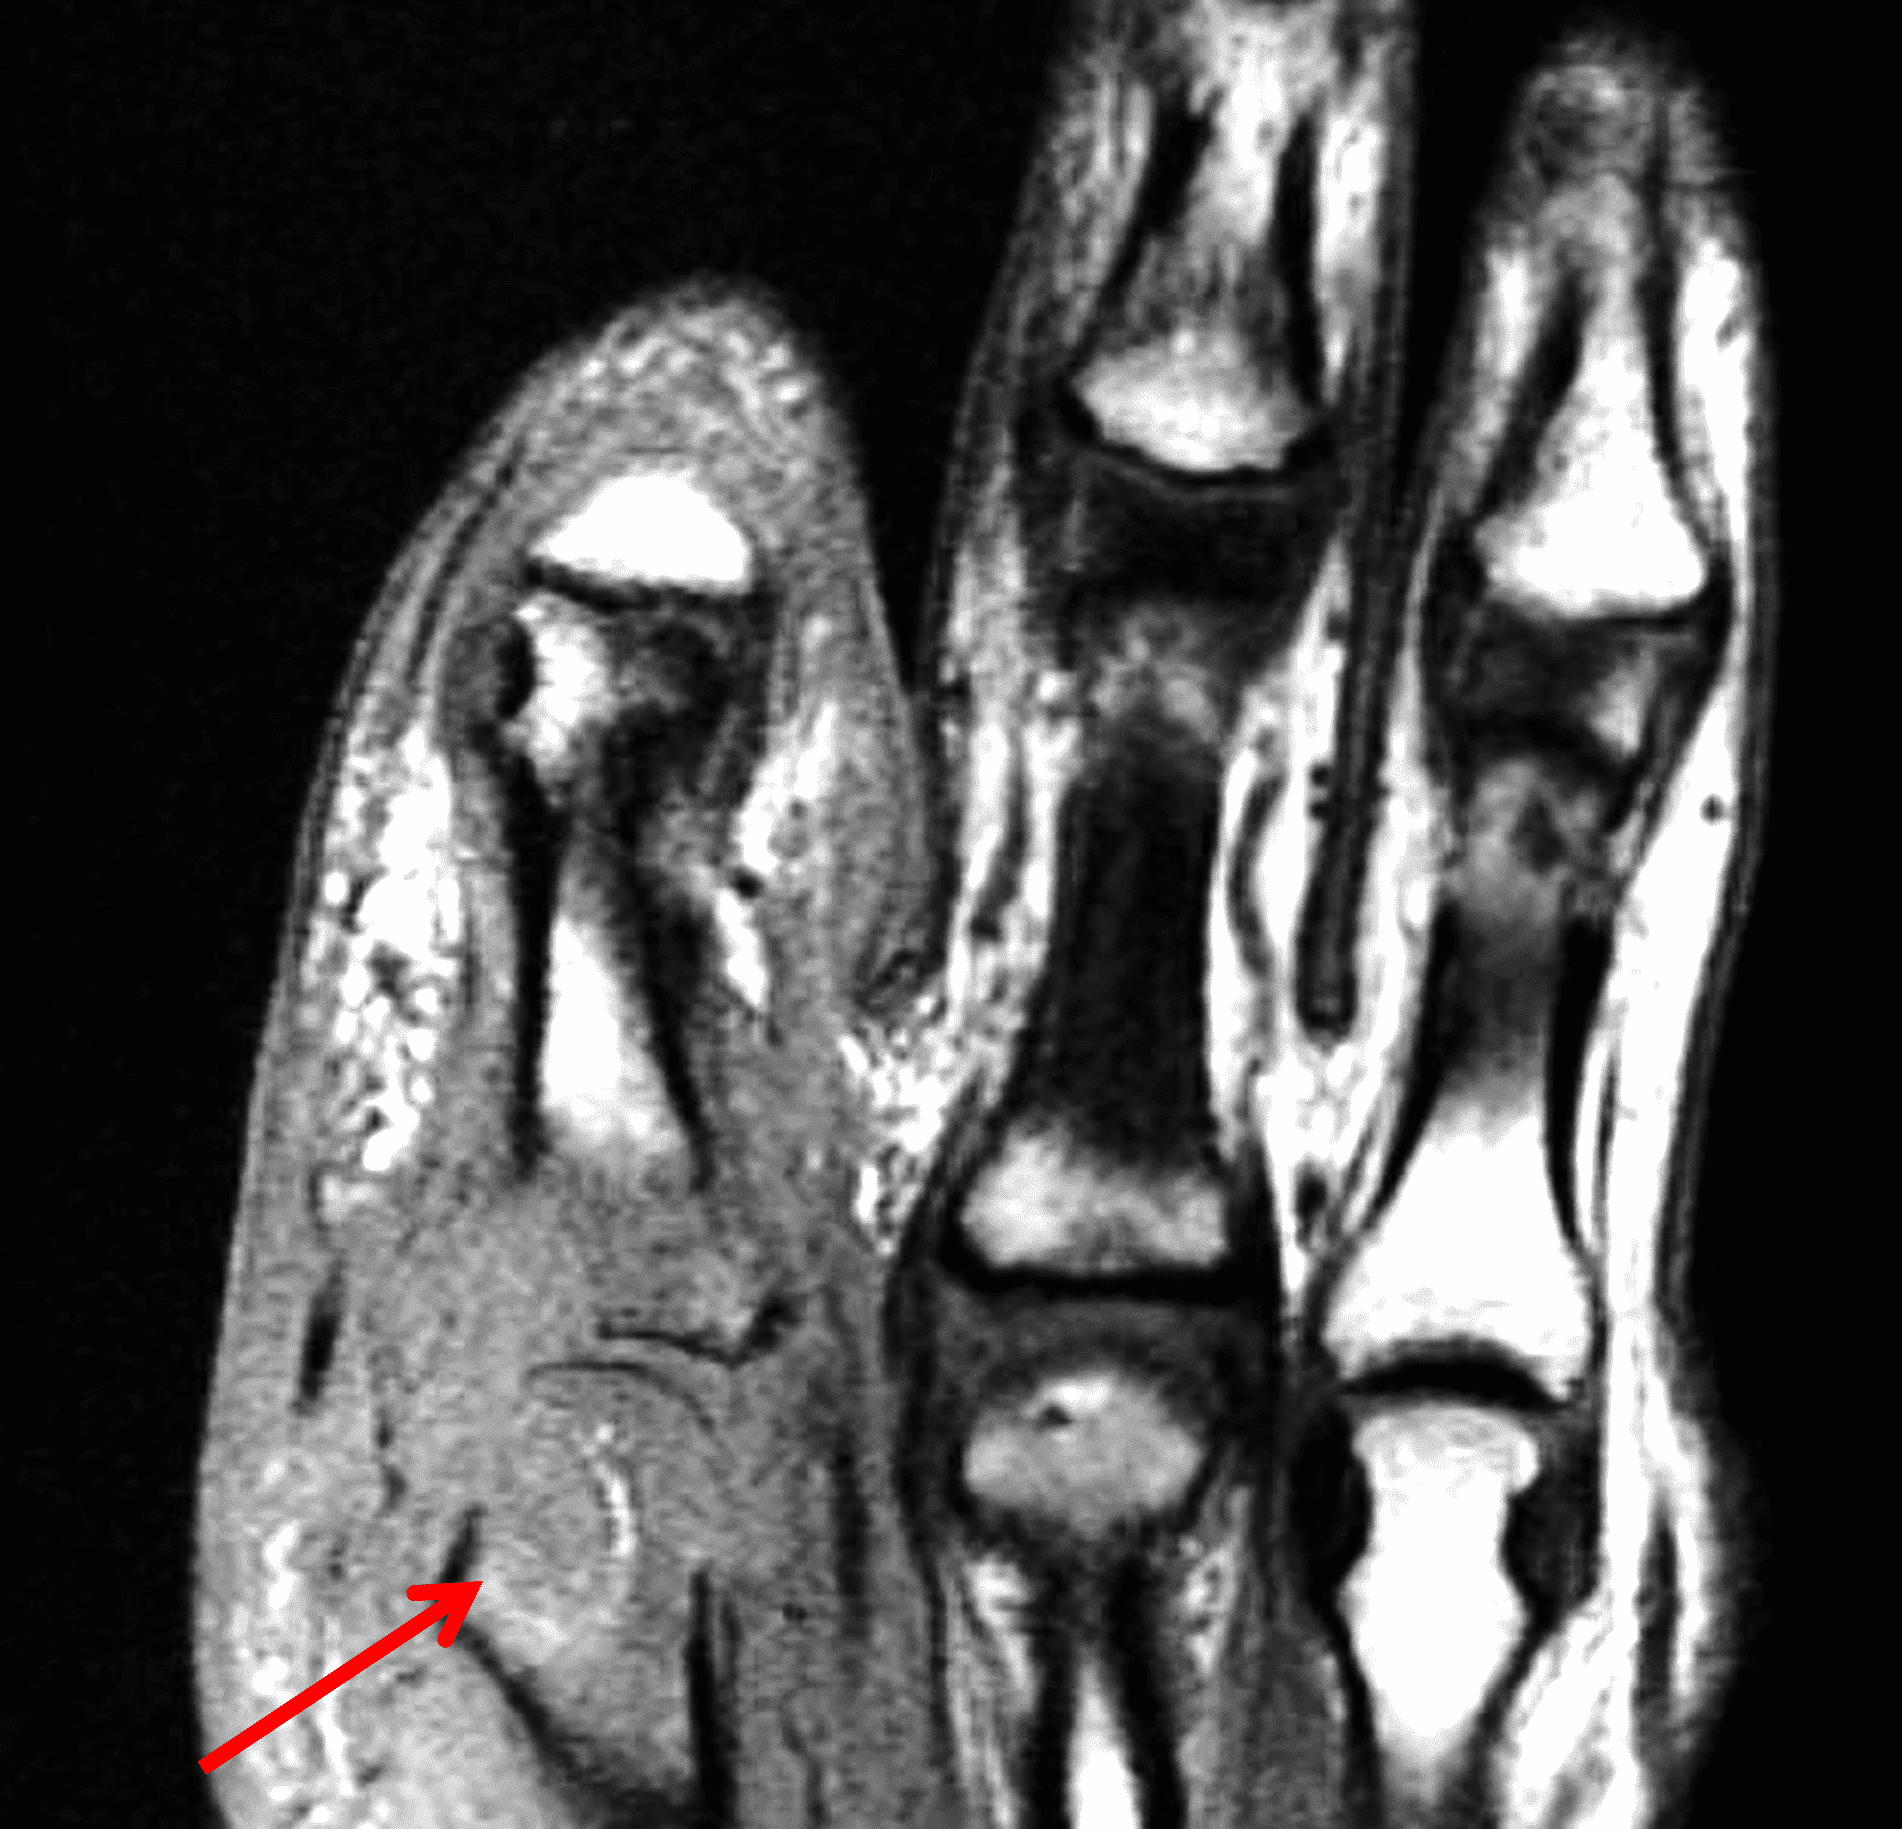

Additional intra-articular processes include but are not limited to: neuropathic osteoarthropathy, osteoarthrosis-related synovitis, septic arthritis (Figure 15), plica related pathology, articular xanthoma, reactive processes related to hardware, and trauma-related findings including lipohemarthrosis.2,3,29

Figure 15: Septic arthritis involving a metacarpophalangeal joint. Long axis (15A) T1-weighted and (15B) fat-suppressed fluid sensitive (15B) images of the finger demonstrate extensive soft tissue edema, joint effusion with osteochondral destruction, diffuse marrow infiltration and an intra-osseous abscess (arrows). Note the high-signal-intensity peripheral rim (“penumbra sign”) around the abscess on the T1-weighted sequence.